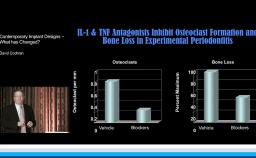

This lecture presents histomorphometric studies to demonstrate the strong relationship between bone and implant design, especially at the implant-abutment interface. The presenter shares key factors to explain the response of hard and soft tissue at the very first step of osseointegration. He focuses on the interaction between the design of the implant and the bone physiology. He develops the relationship between bone resorption and the inflammatory response of the host. The presenter also discusses different ways to decrease the inflammatory response at the implant-abutment interface. Supported by literature, a complete review of the various implant designs and their interactions with the bone is presented. The three major implant types are discussed: one-piece implant; two-piece implant with butt-joint interface; and two-piece implant with platform switching connection. This is a cutting edge lecture on the bone-implant relationship.